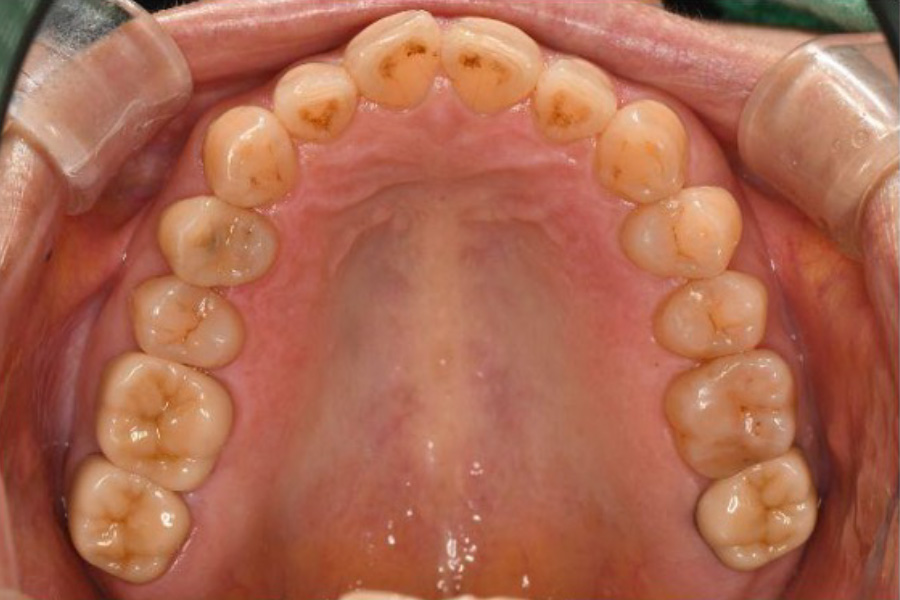

【口腔内写真】上顎咬合面

(上あごの噛み合わせ)の全景

上あごにおいても、歯を支える骨の幅が異常に大きく発達(骨隆起)しています。これは想定を超えた破壊的な荷重(オーバーロード)から歯を守ろうと、身体が必死に地盤を補強した痕跡です。

右上奥歯(6・7番)は、エナメル質が激しくすり減り、内部の象牙質が広範囲に露出しています。歯と歯の継ぎ目には荷重による「ヒビ(クラック)」が入り、そこから細菌の二次侵入を許しています。このまま放置すれば、いずれ歯が真っ二つに割れてしまう寸前の状態でした。

左上奥歯も同様に、重機で削り取ったかのような激しいすり減りが認められます。金属の被せ物には、繰り返された噛み合わせ調整の跡が深く刻まれており、いかに特定の部位に凄まじい力が集中していたかを物語っています。

お口全体の各所に見られる「ヒビに伴う虫歯」は、単なる磨き残しではなく、過度な力による構造破壊が引き金となって細菌の侵入を招いたものであり、根本的な「力のコントロール」が不可欠であることを示しています。